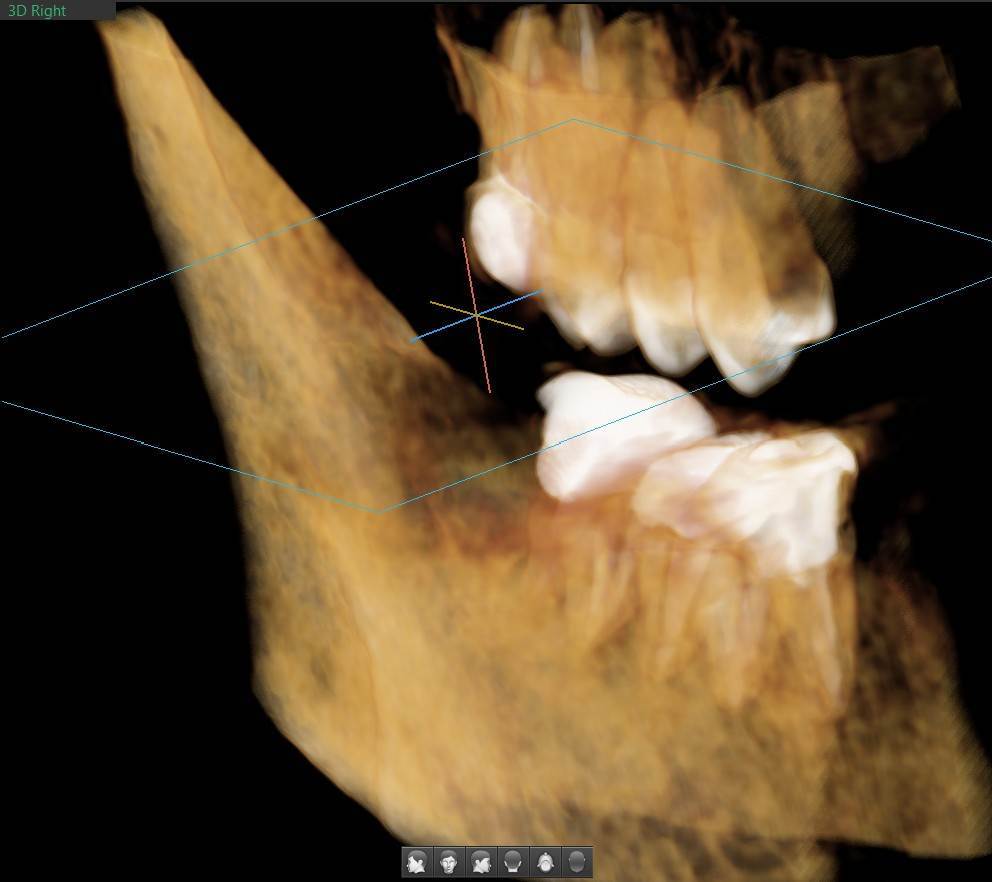

A-V-S Опубликовано 3 марта Поделиться Опубликовано 3 марта Здравствуйте. У меня такая ситуация: В начале января 2026 начал болеть зуб 7ка снизу слева - боль развивалась постепенно - в итоге стало больно жевать. Сделал КТ. Лечащий стоматолог сказал, что это проснулось спящее воспаление, перелечивать каналы зуба сложно - надо сверлить буром и доставать стекловолоконный штифт - надо удалять. В следующие дни открылся свищ и боль ушла. Свищ продолжает быть с периодическим набуханием и сдуванием после выброса гноя белого цвета. Этот зуб лечили с установкой стекловолоконного штифта чуть больше 5 лет назад. Посмотрите, пожалуйста, приложенные снимки и посоветуйте как быть - можно ли перелечить и сохранить зуб ? Ссылка на комментарий

red_butler Опубликовано 4 марта Поделиться Опубликовано 4 марта Здравствуйте, Вы выложили не срезы. а реконструкцию. Залейте кт в облако и скиньте сюда ссылка на скачивание Ссылка на комментарий

A-V-S Опубликовано 4 марта Автор Поделиться Опубликовано 4 марта @АнтонТЛТ, Залил КТ -> https://disk.yandex.ru/d/JJPWXUf3R5E0Xw @red_butler , спасибо. Ссылка на комментарий

Гарриевич Опубликовано 6 марта Поделиться Опубликовано 6 марта Не знаю обрадует Вас это или огорчит, но зуб можно сохранить соседний тоже с воспалением кстати 1 1 Ссылка на комментарий